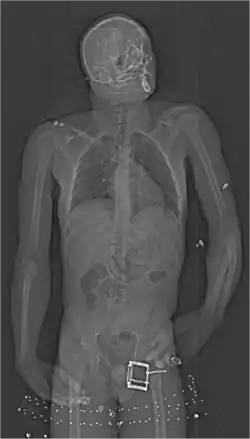

Mule

De nombreuses méthodes existent pour tenter de passer les produits en les camouflant des façons les plus diverses, une des plus impressionnantes étant celle où les produits sont transportés dans le système digestif. Les stupéfiants sont conditionnés en petits sacs étanches et ces petits sacs sont ensuite gobés par la mule. Les douaniers ont dû mettre en place de nouveaux systèmes de détection contre ce trafic, comme notamment la prise de radiographies ou la surveillance des passagers (une mule ne s’alimentera pas et ne boira pas pendant le voyage). Il arrive régulièrement qu’un des sacs se rompt sous l’effet des sucs gastriques ou du fait d'un emballage défectueux, entraînant éventuellement la mort de la mule par surdose[34],[35]. Les films Maria, pleine de grâce et Lucy y sont consacrés.